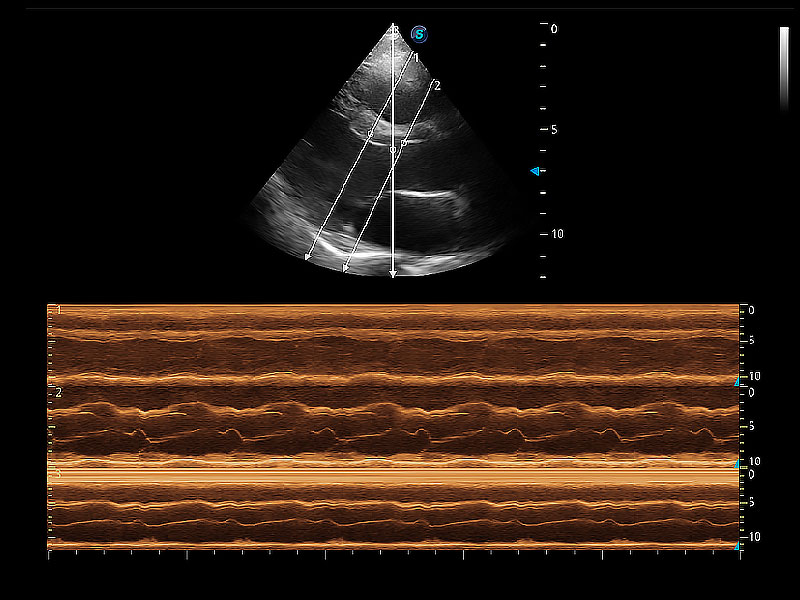

ProPet 80 配備了豐富的心臟探頭群、先進(jìn)的成像技術(shù)和專業(yè)的心臟測量工具,可幫助動物醫(yī)生為不同體型和生理結(jié)構(gòu)的動物提供心臟和心肌功能的全面評估。

通過360度任意調(diào)節(jié)3條M型取樣線,在同一心動周期上觀察心臟不同位置的運(yùn)動曲線,得到準(zhǔn)確的心功能測量數(shù)據(jù),有效評估心肌運(yùn)動及左心室功能。